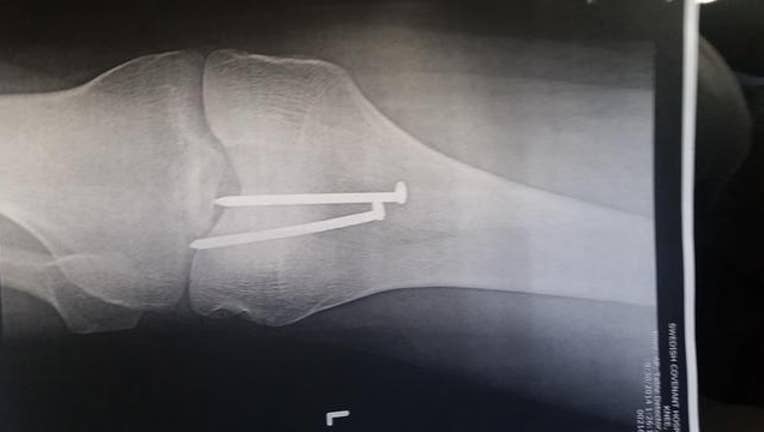

A Chicago man who was working just his second day at a new job is recovering after shooting himself in the kneecap with a nail gun.

He was sheeting the roof when he had to step over the gap between two units. As he stepped over, he mistakenly landed on the gas hose connected to the gun. The gun jerked forward and the front of it met directly with the top of his knee, shooting two 16 gauge wood framing nails directly into the top of his knee.

A co-worker rushed him to the hospital to have the two nails removed, but not before taking an X-ray, which he got a picture of. He also snapped pictures of the heads of the nails in his knee - but those are extremely graphic.

After getting the nails removed, six different doctors came in to tell him how lucky he was for the nails to land where they did. The nails didn't hit any bone, they went between his kneecap and femur. How lucky is that?